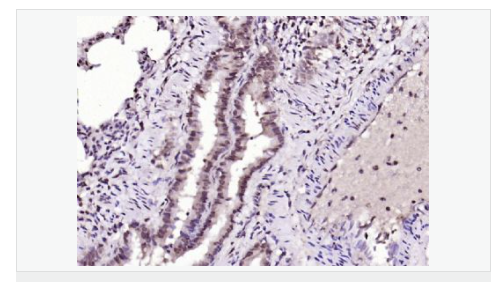

| 產(chǎn)品應(yīng)用 | ELISA=1:5000-10000 IHC-P=1:100-500 IHC-F=1:100-500 IF=1:100-500 (石蠟切片需做抗原修復(fù)) not yet tested in other applications. optimal dilutions/concentrations should be determined by the end user. |